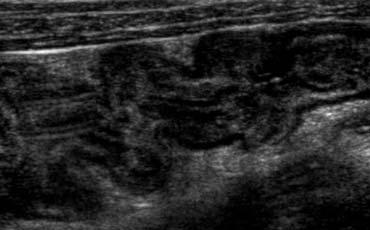

Lâm sàng nghi viêm ruột thừa. Siêu âm chỉ phát hiện một lượng nhỏ dịch cổ trướng. Chọc dò chẩn đoán (mũi tên chỉ đầu kim) cho thấy dịch máu. Ở phụ nữ, phát hiện này rất nghi ngờ thai ngoài tử cung (EUG).